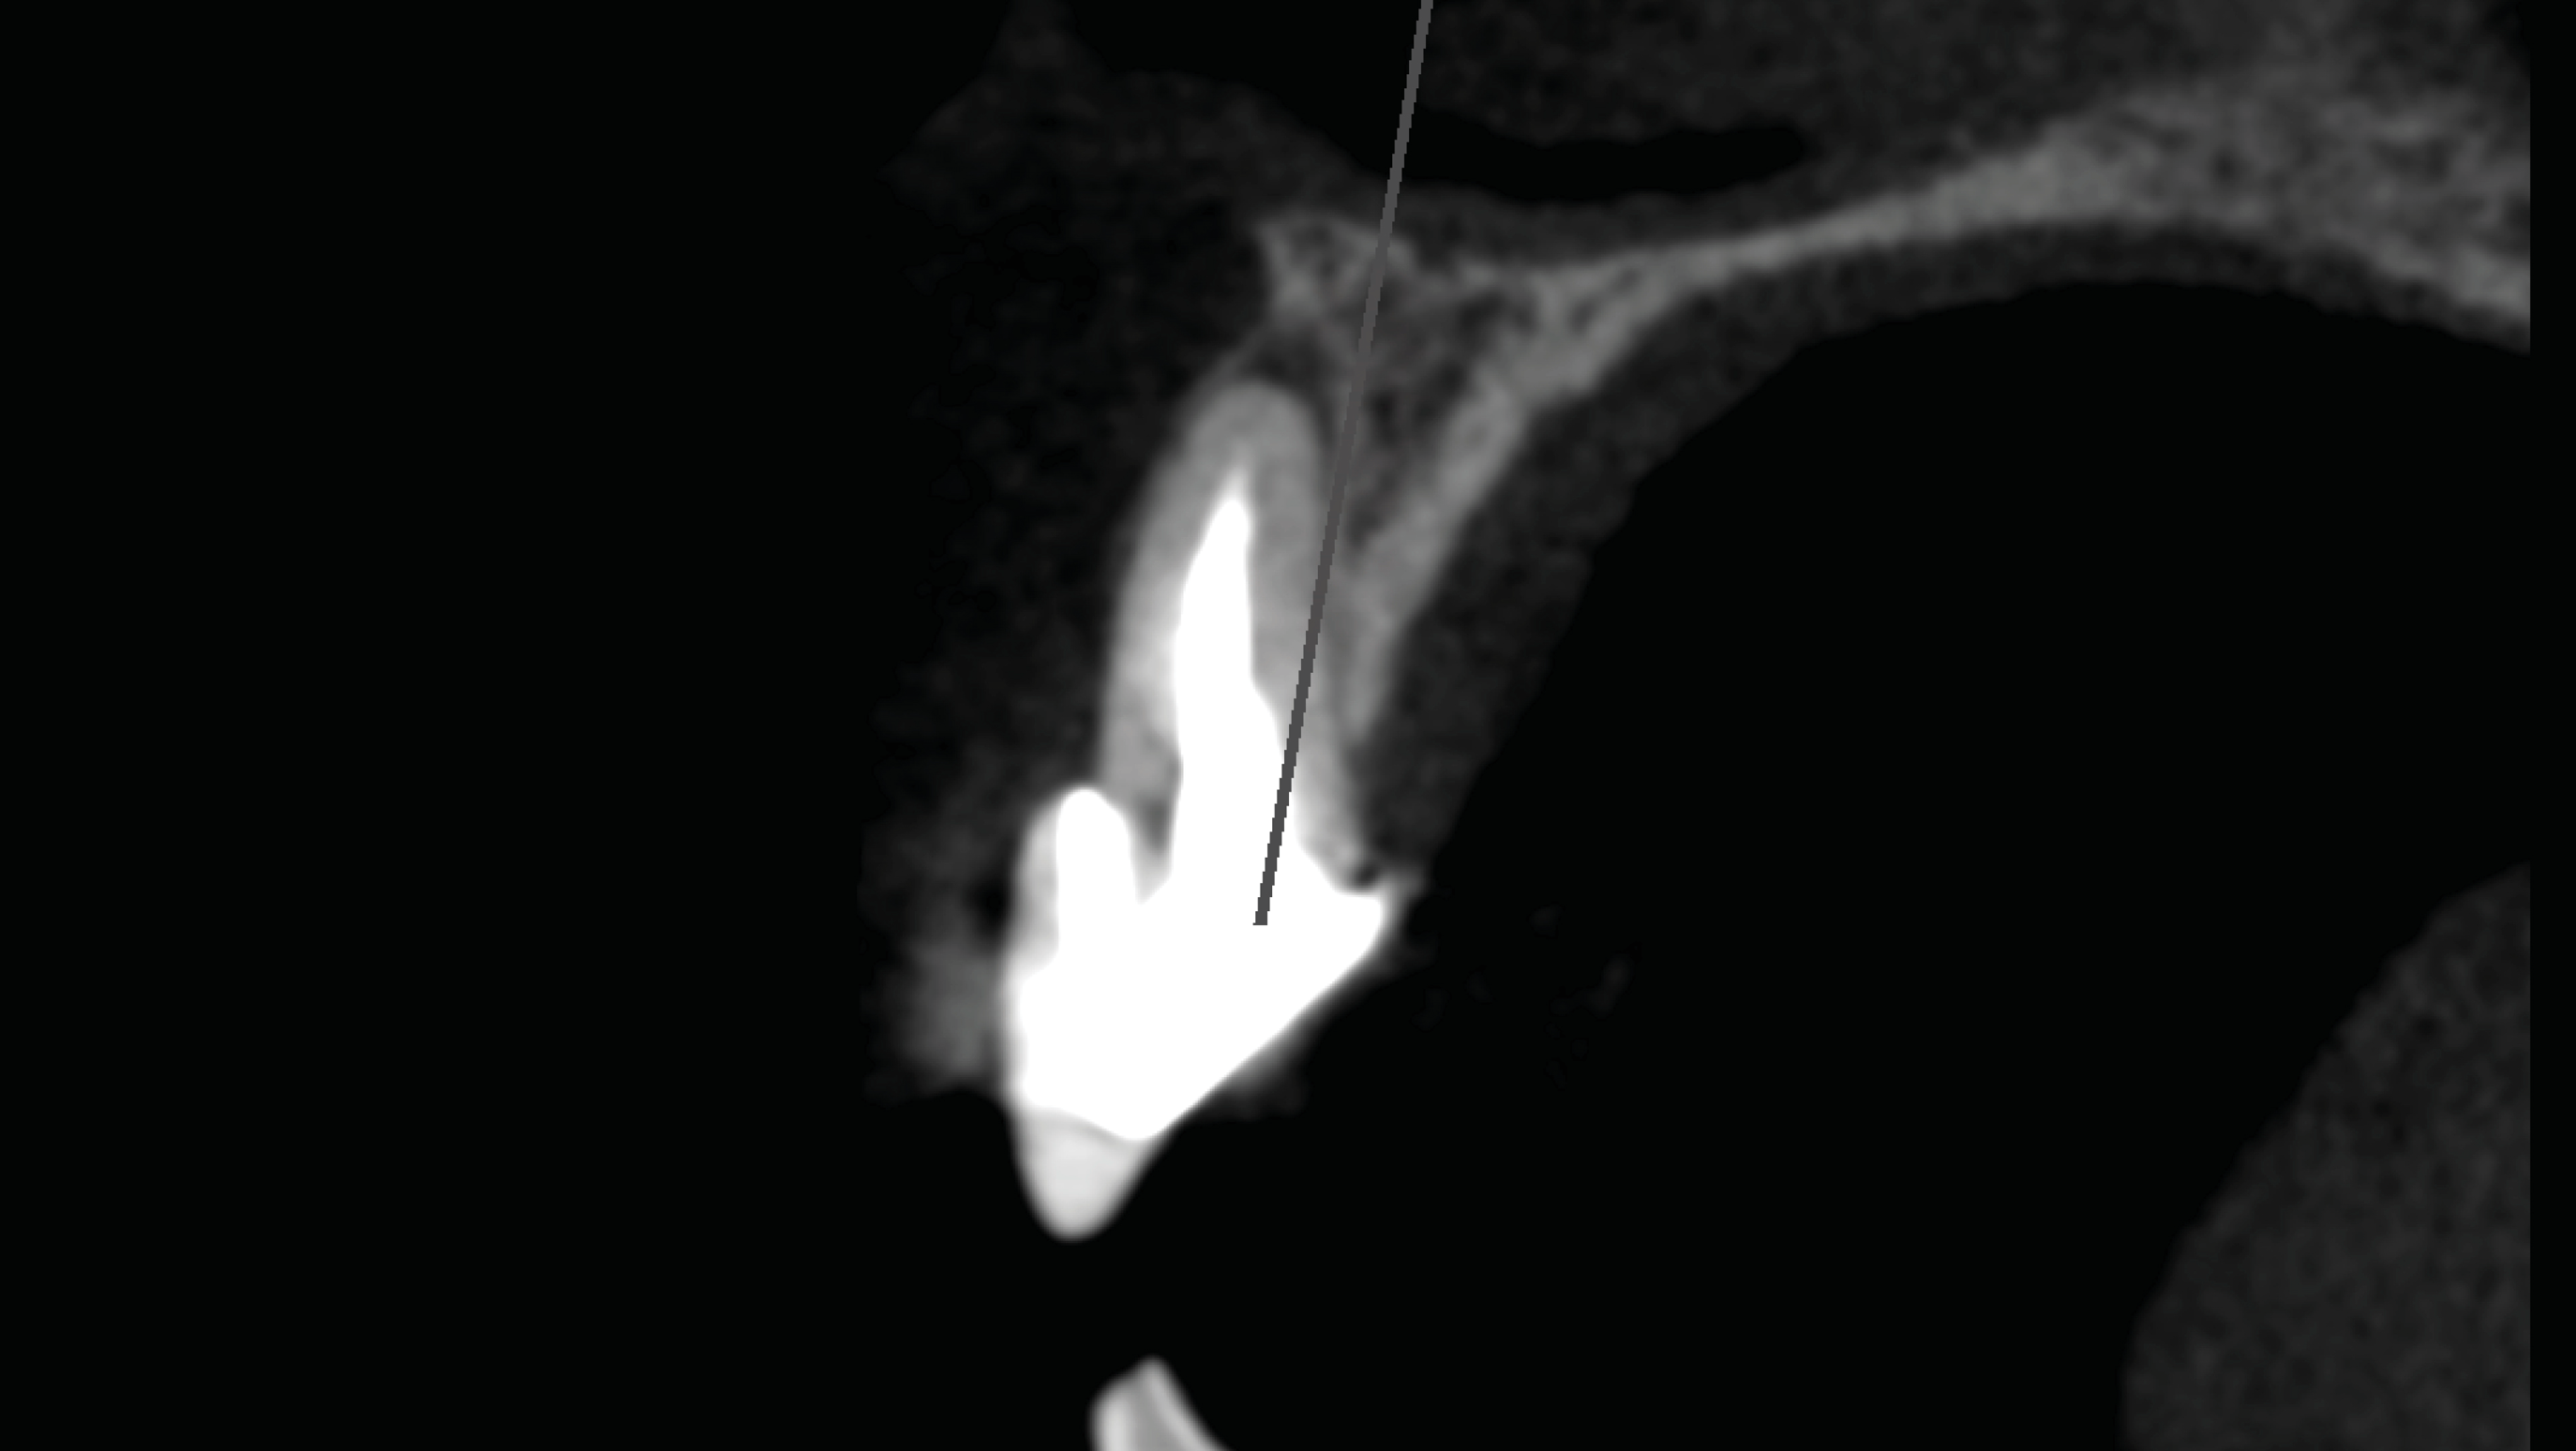

The procedure begins with the use of cone-beam computed tomography (CBCT) to measure the length of the tooth from the apex to the incisal edge, the length between the apex and the gingival margin, and the distance from the gingival margin to the buccal bone level. Obtaining CBCT images with a retracted vestibule is a requisite.19 Merging intraoral scan standard tessellation language (STL) images to a CBCT scan can be a helpful additional diagnostic tool. In summary, the CBCT imaging is used to verify and measure alveolar bone width and length, root length in bone, soft tissue to bone crest, bone crest to tooth apex, alveolar bone height, and implant position (Figure 2 through Figure 4).

Fig 3. Initial diagnostic CBCT.

Figure 3

Fig 4. Diagnostics measurements include alveolar bone height, root length in the bone, and distance from the gingival margin to the buccal bone level.

Figure 4